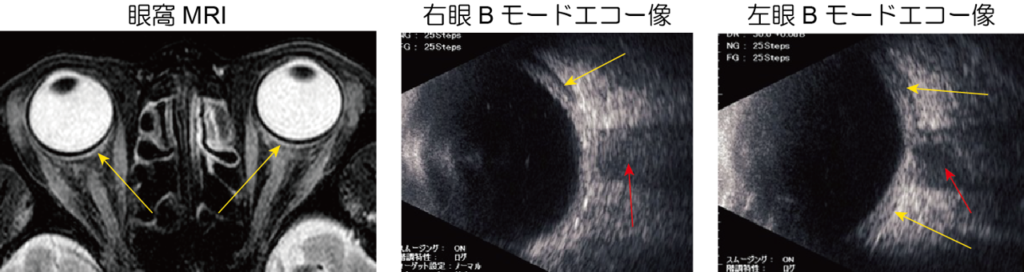

後部強膜の炎症による肥厚と浮腫の画像化にはCT、MRI、超音波検査などが必要です。

超音波Bモードエコーでの眼球後壁に沿う浮腫による低反射像は視神経の低反射像と連続するためTサインと呼ばれます。

眼痛は訴えませんが、充血の強かった3か月前には強い頭痛があったとのことで眼窩を含めた頭部MRI撮影を行ったところ、両眼球の後壁に沿ってT2WIで高信号の浮腫像(図左矢印)がみられました。

そこで超音波Bモード検査も行ってみると眼球後壁に接する低反射像(図中央、右の黄矢印)が視神経(赤矢印)に連なるTサインが両眼ともにみられ、後部強膜炎と診断しました。